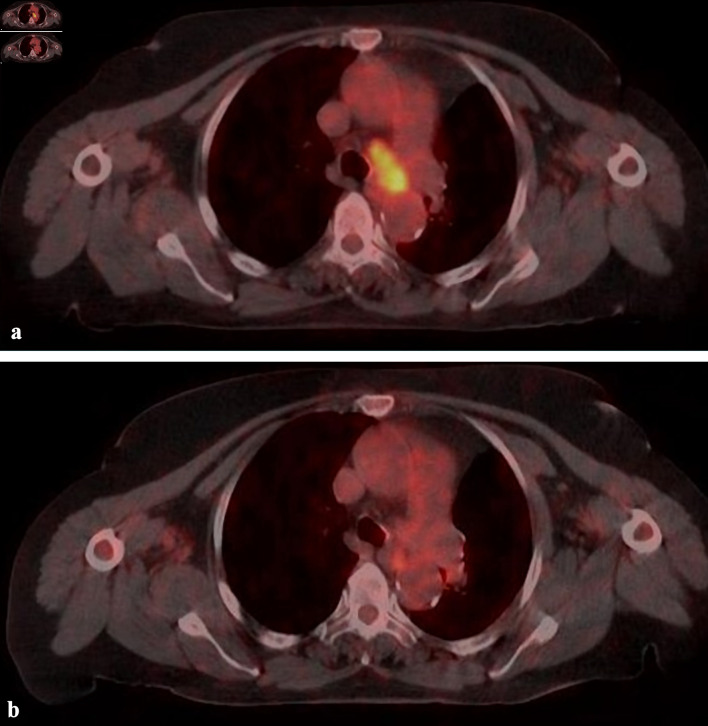

Methods: Forty-two lesions from 35 patients were treated between 2019 and 2022. Four-dimensional computed tomography images were obtained when the patients were in a free breathing modality. Tracking modality was selected prospectively according to the visibility of the target. The median prescribed dose was 48 Gy in four fractions (fx) (28 - 55 Gy/1- 7 fx). The median age was 68 years (47 - 82 years), and 43% of cases were adenocarcinoma. The median lesion size was 15 mm (6 - 36 mm).

Results: Complete, partial and stable responses were obtained as 26%, 62%, and 9.5% at a median of 2 months (1 - 6 months), and 35.5%, 47.5% and 5% at the 12th month evaluation, respectively. Grade 3 and higher toxicity was not observed in any case. The mean and 2-year overall survival (OS) was 31.5 months and 54%, and the local recurrence-free survival (LRFS) was 29.6 months and 51%, respectively. In univariate analysis, target lesion type, complete response (CR), and higher esophagus maximum dose were favorable factors for OS and LRFS (P < 0.05). The CR at 12th month evaluation remained significant in multivariate analysis in terms of OS (hazard ratio = 8.602, 95% confidence interval: 1.05 - 70.01; P = 0.044).

Conclusions: A mean LRFS of 29.6 months and OS of 31.5 months were obtained in patients with primary and metastatic lung cancer. With a median treatment time of 25 min, motion-managed strategy with CK-M6-LOT-based SBRT is an effective, safe, and comfortable treatment method for lung cancer.